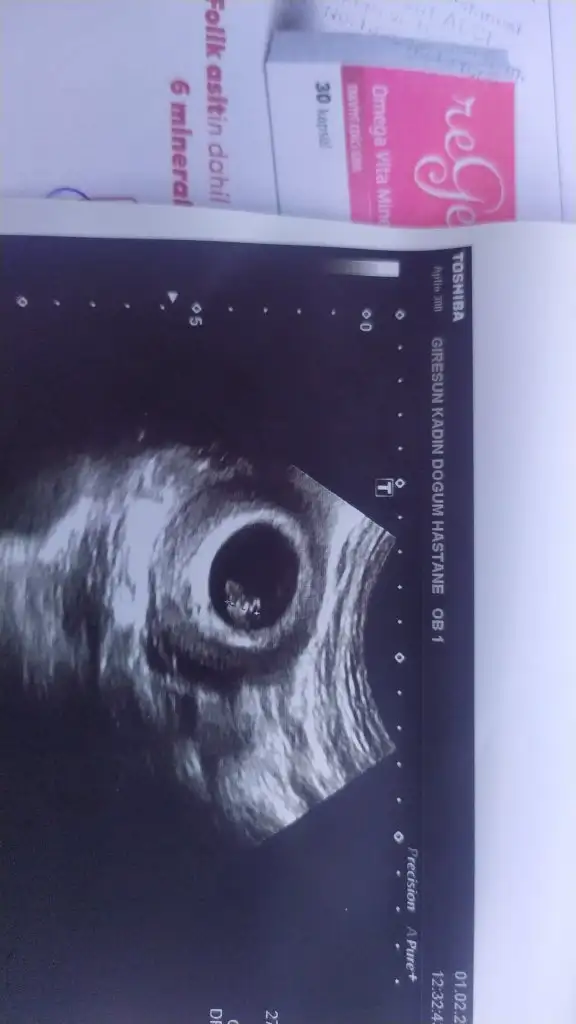

Kızlar aramızda keseye vs bakıp cinsiyet tahmini yapan var mı 😂😂karından 6+4

KUZU şimdi kesenin şekli yuvarlaksa tezi var. benimki yuvarlaktı. dün gittim baktım aha yuvarlak gene sonra doktor açı değiştirdi kese yassılaştı :D o sebeple kese şekliyle cinsiyet olayı bana saçma geldi cunku ikisinide gördüm. ultrasonu basgtırınca sekli değişti :D 10 gun onceki kese seklim yuvarlak. dün verdiği fotograf cıktısında yassı gorunuyo ama ekranda yuvarlak resmi de gorduk. bebek net diye yassı olanı cıkardı. belki ilk kese olustugu hali belirteçtir. gelelim 2. secenek bebegın plesantası yenı olsurken sagda olusuyor bebek soldaysa kız tersiyse erkek. senin ne tarafta . sanki altında. benim bilgiler buraya kadar tükendi :D :D

Hadi kızlar kese tahmini 🤣🤣🤣🤣

Eklentiler

• IMG-20240201-WA0014.webp

IMG-20240201-WA0014.webp

16,8 KB · Görüntüleme: 64